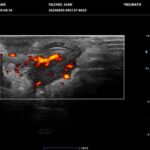

La HS es una enfermedad crónica, inflamatoria inmunomediada, sistémica, recurrente y debilitante de los folículos pilosos terminales con origen en las glándulas apocrinas de estos. Presenta habitualmente lesiones dolorosas, profundas e inflamadas, localizadas más frecuentemente en las regiones axilares, inguinales y anogenitales. El 80% de las lesiones tienen ubicación profunda de difícil acceso al examen físico. Su diagnóstico es clínico pero el ultrasonido (US) de alta resolución con Doppler es un método que cumple actualmente un rol esencial para establecer el diagnóstico, estadificar la enfermedad y detectar actividad, incluso en el caso de lesiones no pesquisadas en el examen físico. También nos permite monitorear el estado y la progresión de la HS, facilitando la evaluación rápida de distintos enfoques terapéuticos. Incluso, los cambios ecográficos pueden modificar la conducta terapéutica.

Hallazgos imagenológicos

Los hallazgos ecográficos más relevantes son el ensanchamiento de folículos pilosos, engrosamiento y ecogenicidad anormal de la dermis, nódulos pseudoquísticos dérmicos, colecciones líquidas y tractos fistulosos. Por otro lado, el US nos permite valorar la localización exacta y extensión de las lesiones, su ecogenicidad, el grado de vascularización al examen Doppler y las eventuales complicaciones, e incluso la modificación de las lesiones en respuesta a la terapéutica instaurada. La HS se estadifica clínicamente mediante la clasificación de Hurley y los hallazgos ecográficos muestran correlación con cada estadio clínico.

El diagnóstico ecográfico resulta de importancia diagnóstica, tal es así que la ecografía de alta resolución y el estudio Doppler han ocupado un lugar preponderante en los últimos años. La ecografía de la piel permite identificar lesiones no encontradas en el examen físico, evaluando de manera fehaciente su extensión anatómica. El empleo de la ecografía en la HS es ideal, ya que el 80% de las lesiones ocurren en las capas más profundas y no en la superficie de la piel. Permite evaluar la localización exacta y extensión de las lesiones, su ecogenicidad, el grado de vascularización al examen Doppler, las eventuales complicaciones, e incluso la respuesta terapéutica.

El estudio ecográfico de alta resolución con Doppler tiene un rol fundamental en la categorización de las lesiones de HS en profundidad, incluso las subclínicas. Debemos incluir al US como técnica de elección para estadificar y monitorear pacientes con HS, ya que nos permite acceder a un diagnóstico rápido de lesiones típicas con las que podremos, en conjunto con la clínica, estadificar y seguir en el tiempo a los pacientes.